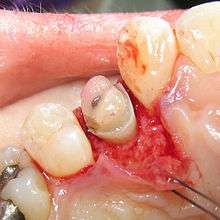

A palatal view of a maxillary premolar during a crown lengthening procedure.

Crown lengthening is a surgical procedure performed by a dentist to expose a greater amount of tooth structure for the purpose of subsequently restoring the tooth prosthetically.[1] This is done by incising the gingival tissue around a tooth and, after temporarily displacing the soft tissue, predictably removing a given height of alveolar bone from the circumference of the tooth or teeth being operated on. While some general dentists perform this procedure, others frequently refer such cases to periodontists.